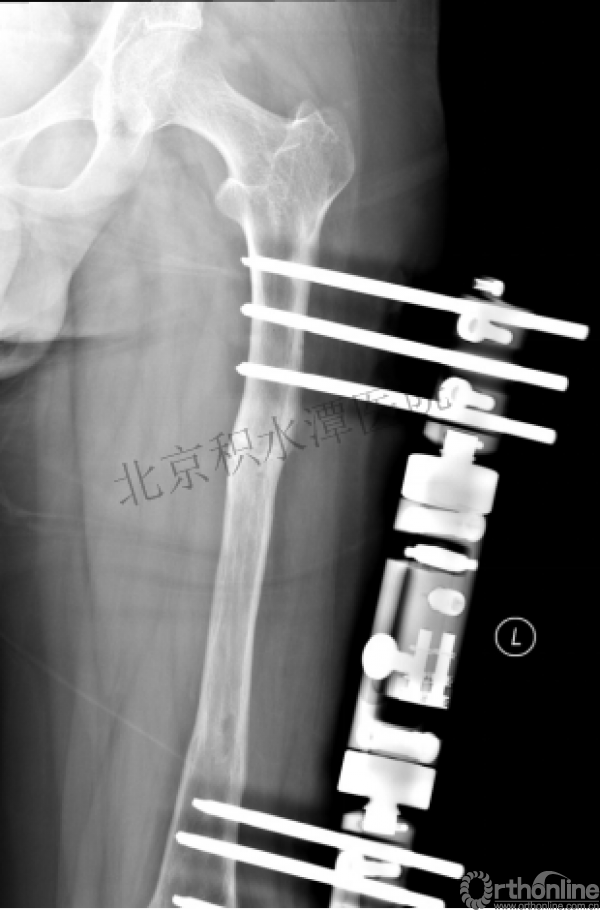

外固定架术后一年

整整11年!是否治疗终结?

病人的付出?医生当反思!

1.使用了医生可以使用的所有固定方式

2.似乎哪一次的处理都没有违背原则

3.问题出在哪儿?

4.骨折治疗—手术不是万能的!